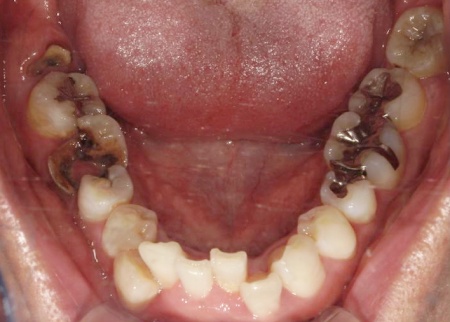

まずは、温存が難しいと判断した以下の歯を抜きます。

右上

・4番目(第1小臼歯)

・6番目(第1大臼歯)

左上

・5番目(第2小臼歯)

・8番目(第3大臼歯)

右下

・8番目(親知らず)

感染が周囲に広がらないよう配慮しながら、慎重に抜歯を行いました。

抜歯後は骨や歯茎の回復を待ち、口腔内の状態が安定した段階で、インプラント埋入手術へ進みました。